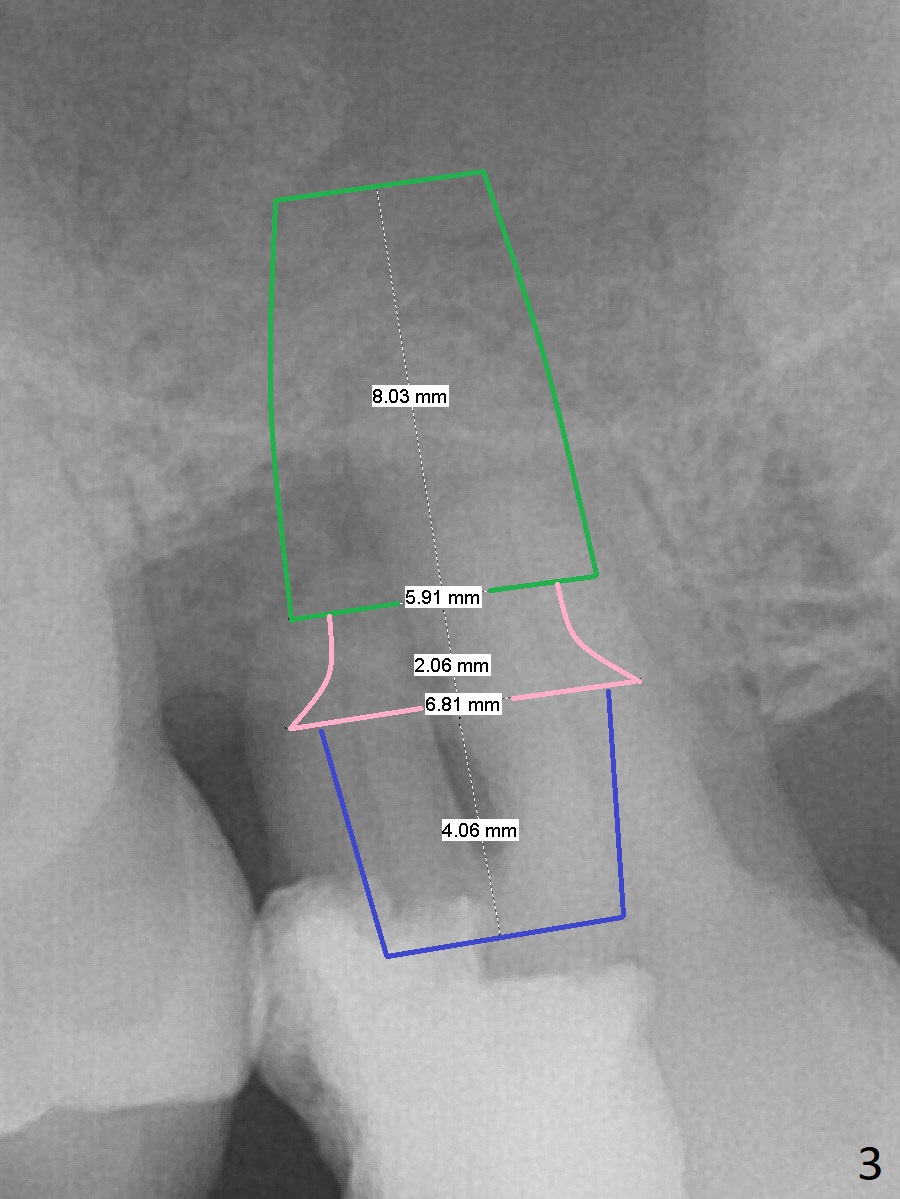

A 47-year-old man will return for #15 extraction and implant (Fig.1). Bone loss seems to be the most severe around the mesiobuccal root (Fig.2 *), from which the osteotomy should stay away (Fig.3). Take PVS impression for the sockets. Use Tatum osteotomes for sinus lift.